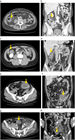

1. 大腸憩室炎と大腸憩室出血の典型例

大腸憩室炎

1. 大腸憩室炎は急性期に、膿瘍形成、腸閉塞、瘻孔形成、穿孔、腹膜炎などの状態を合併することがある。